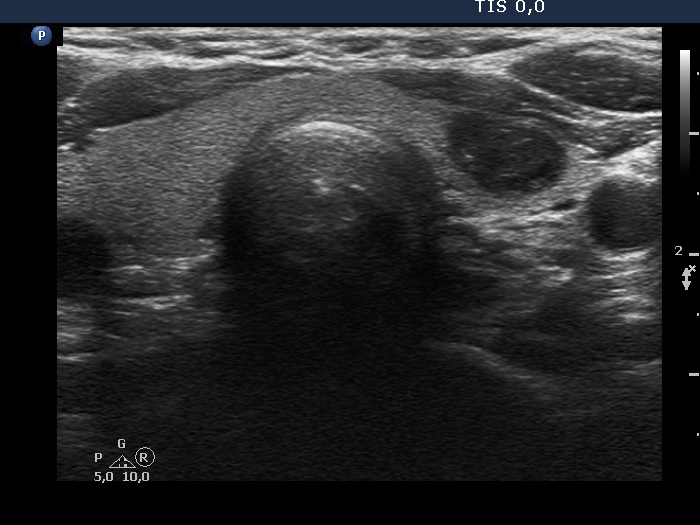

Five months after the first examination (third row of images)

Clinical presentation: The patient had no complaints. She was referred for evaluation of an elevated TSH level.

Palpation: no abnormality.

Laboratory tests: 4.76 mIU/L, aTPO 0,6 U/mL.

Ultrasonography. The thyroid was echonormal. There was a hypoechoic nodule in the ventral part of the left lobe. The ventral borders of the lesion were undefined because the echogenicity of the lesion and the neighboring strap muscle was identical.Suggestion: TSH in a year, ultrasound in two years, in the event of complaints at once.

- Compared with the nodule just after the aspiration with that seen five months later, a spontaneous further decrease can be observed.

- On the second examination, we cannot see cystic portions, therefore the intranodular echogenic figures might cause concern. However, if we take the ultrasound pattern at the previous examination into account, this concern is not justified.

- The presentation of the nodule at the follow-up is an example of non-pathological cause of blur.